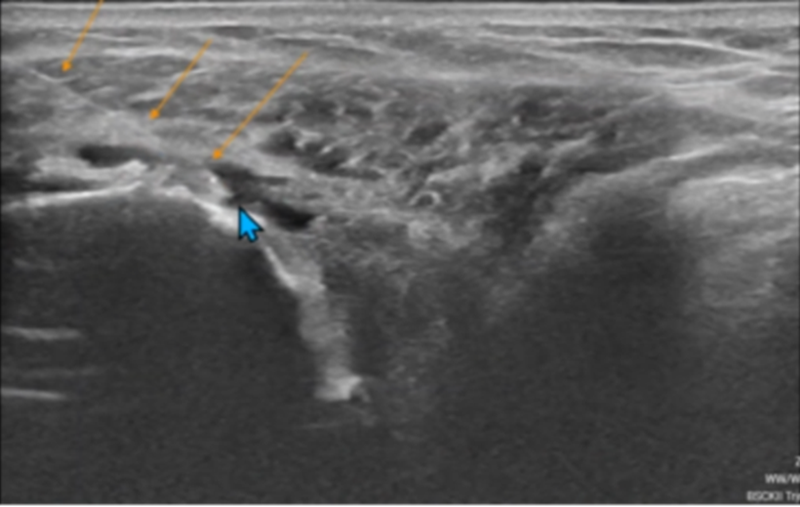

Hình ảnh tiêm nong khớp vai dưới hướng dẫn siêu âm tại MEDLATEC

Ngay lập tức bà H. được chỉ định tiêm thuốc chống viêm và gỡ dính bao khớp vai, sau đó kết hợp tiêm huyết tương giàu tiểu cầu để tránh tái phát. Bệnh nhân cũng được tư vấn tập phục hồi chức năng (tránh tập động tác xoay vai), song song điều trị thuốc uống và tiêm khớp.